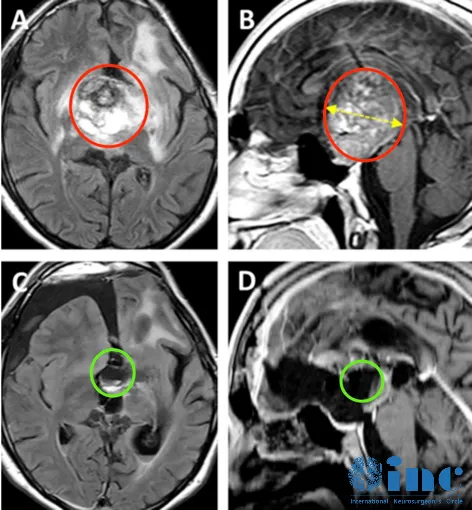

9岁男孩丘脑胶质瘤,手术+化疗效果良好

患者情况:左面部、上肢和下肢有3周的急性病史,持续轻微口齿不清三个月以上。他还有多处咖啡色的斑点和腋窝雀斑。被诊断患有注意缺陷多动障碍,这些症状可以归因于器质性病因。(下图a、b)轴位MRI造影剂及冠状面T2-WI显示一个环形增强的右侧丘脑结节肿瘤。

主诊医生:加拿大多伦多大学儿童医院(SickKids)、INCJames T.Rutka教授团队

治疗过程:Rutka教授考虑根据其病情进展制定综合治疗方案,先行经颞中回经脑室入路次全切除肿瘤,组织学为WHO I级毛细胞星形细胞瘤,BRAF重复融合状态为阴性。免疫组化检测BRAF V600E、H3K27M阴性。基因测试证实了NF1基因的变异。术后严密随访患儿术后情况。

治疗后情况:6个月后的影像显示丘脑部分切除和中脑的小肿瘤残留,因此,Rutka教授根据其病情发展量身定制辅助治疗计划,患儿对放疗反应良好。

术后6个月显示肿瘤次全切除